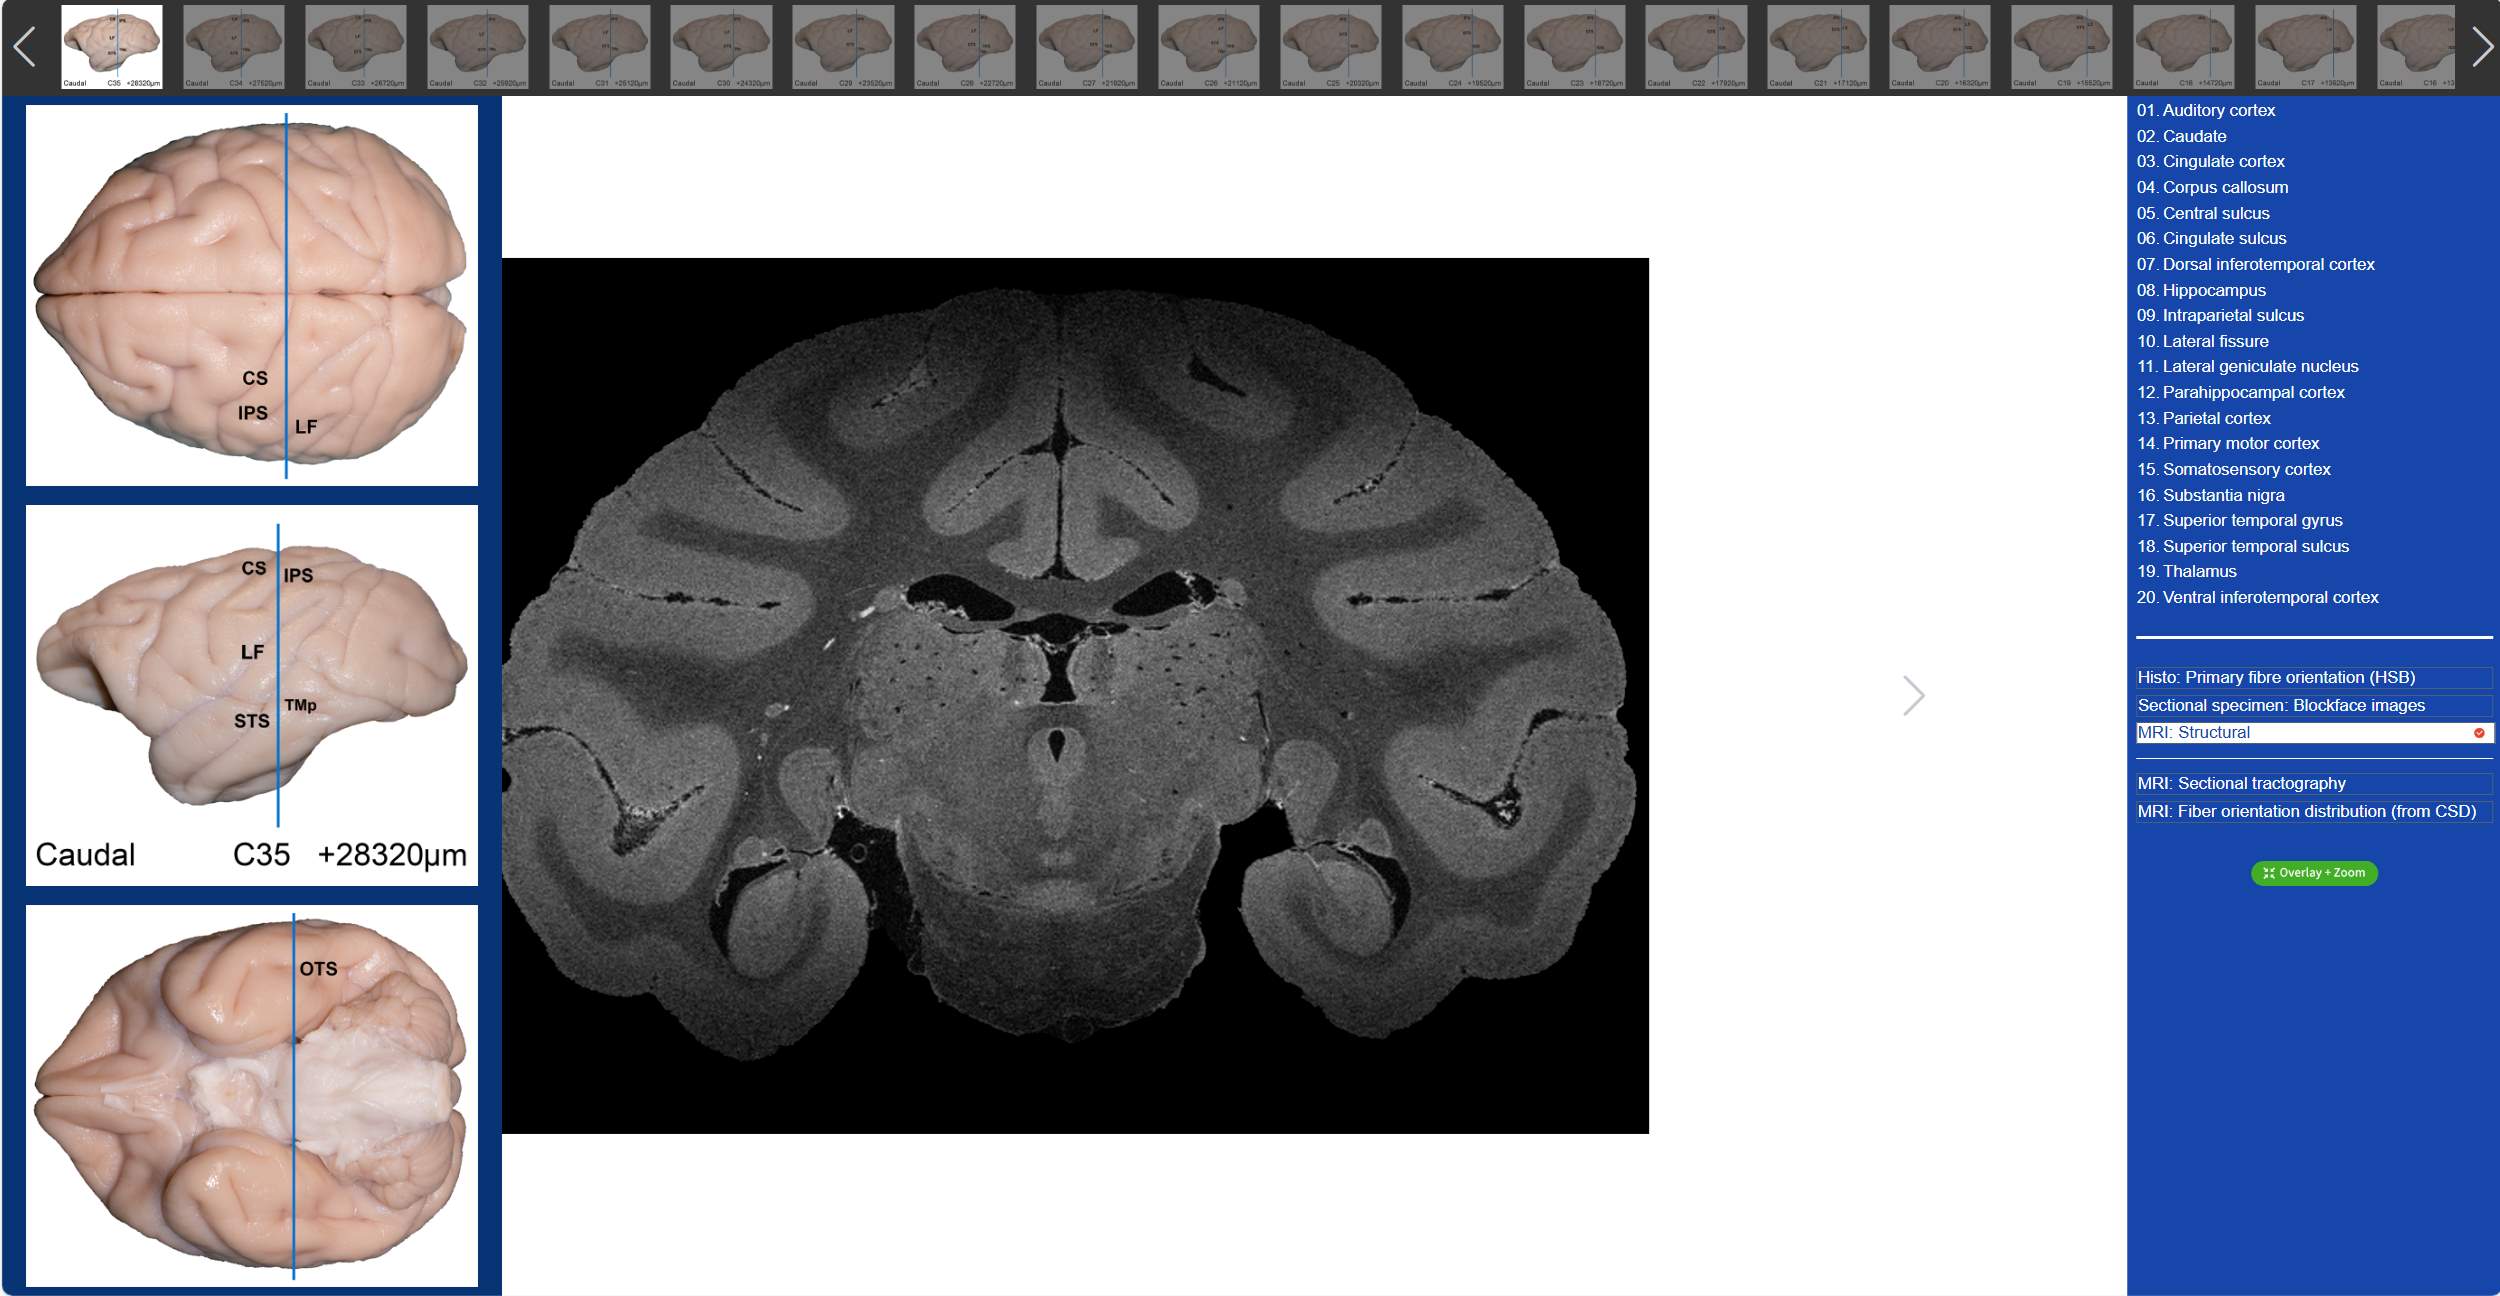

值得一提的是,在“動物腦樂園”里,不僅可以觀察到獼猴3D腦標本,還可以看到獼猴的全腦切片。吳勁松教授團隊從同一猴腦的離體MRI及全腦組織切片髓鞘染色(LFB)數(shù)據(jù)集中,間隔800μm取一層,構(gòu)建了集合組織切片髓鞘染色(LFB)、組織切片髓鞘染色-偽彩化、斷層標本圖、高分辨率MRI結(jié)構(gòu)像及離體腦dMRI斷層纖維束成像和纖維方向分布圖(限制球面反卷積-CSD)六大模態(tài)的斷層對照圖譜。我們只需要點擊相應(yīng)的解剖名稱,就可以在圖譜上對應(yīng)位置顯示標記,同時可與另外兩大模態(tài)的dMRI方向性信息進行對照,極大的方便了我們的觀看。